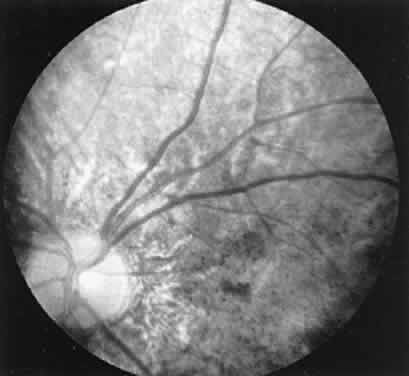

amplitude of the scotopic b-wave in a fully dark-adapted eye.13  Fig. 13. Female carrier of X-linked retinitis pigmentosa. Fundus photographs of

a 48-year-old female with vision of 20/20 OD and OS. Left. Macular area shows an unusual scintillating reflex around the entire parafoveal

region. Right. Retinal periphery showing an isolated area of retinal pigment epithelial

loss with associated clumps of pigment. Fig. 13. Female carrier of X-linked retinitis pigmentosa. Fundus photographs of

a 48-year-old female with vision of 20/20 OD and OS. Left. Macular area shows an unusual scintillating reflex around the entire parafoveal

region. Right. Retinal periphery showing an isolated area of retinal pigment epithelial

loss with associated clumps of pigment.